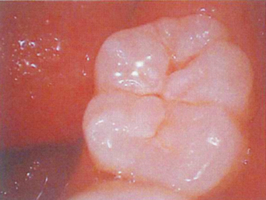

pH5の次亜塩素酸とpH8の炭酸水素ナトリウムが両者ともに同濃度になるpH6.5の次亜塩素酸の生成により、歯や歯肉の組織溶解性がなく歯肉の細胞が固定され細胞形態が変異しません。

60分経過後

pH6.5のため歯肉が溶けず

骨を包囲している